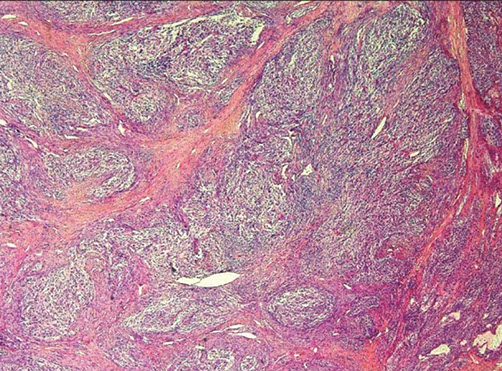

Parathyroid Carcinoma

Up to 2% of pts c hyperparathyroidism, M=F, ~50 yo, inc Ca2+, neck mass

- 1/3 have LN mets and 1/3 c distant mets at presentation

Micro: trabecular, thick fibrous bands, capsular invasion, mits, but need to see invasion into surrounding tissue or distant mets

IHC: (+) Cam5.2, AE1/AE3, PTH, CD56, SYN, CHR

- neg: TTF-1, thyroglobulin, PAX8, parafibromin

Genes: mutations in HRPT2/CDC73 gene on chr 1 which encodes parafibromin

- same gene is mutated in hyperparathyroidism-jaw tumor (HPT-JT) syndrome, which has ossifying fibromas of the jaw, uterine and renal tumors and parathyroid tumors

- PRAD 1, MEN 1, Cyclin D1 overexpression

Tx: surgery